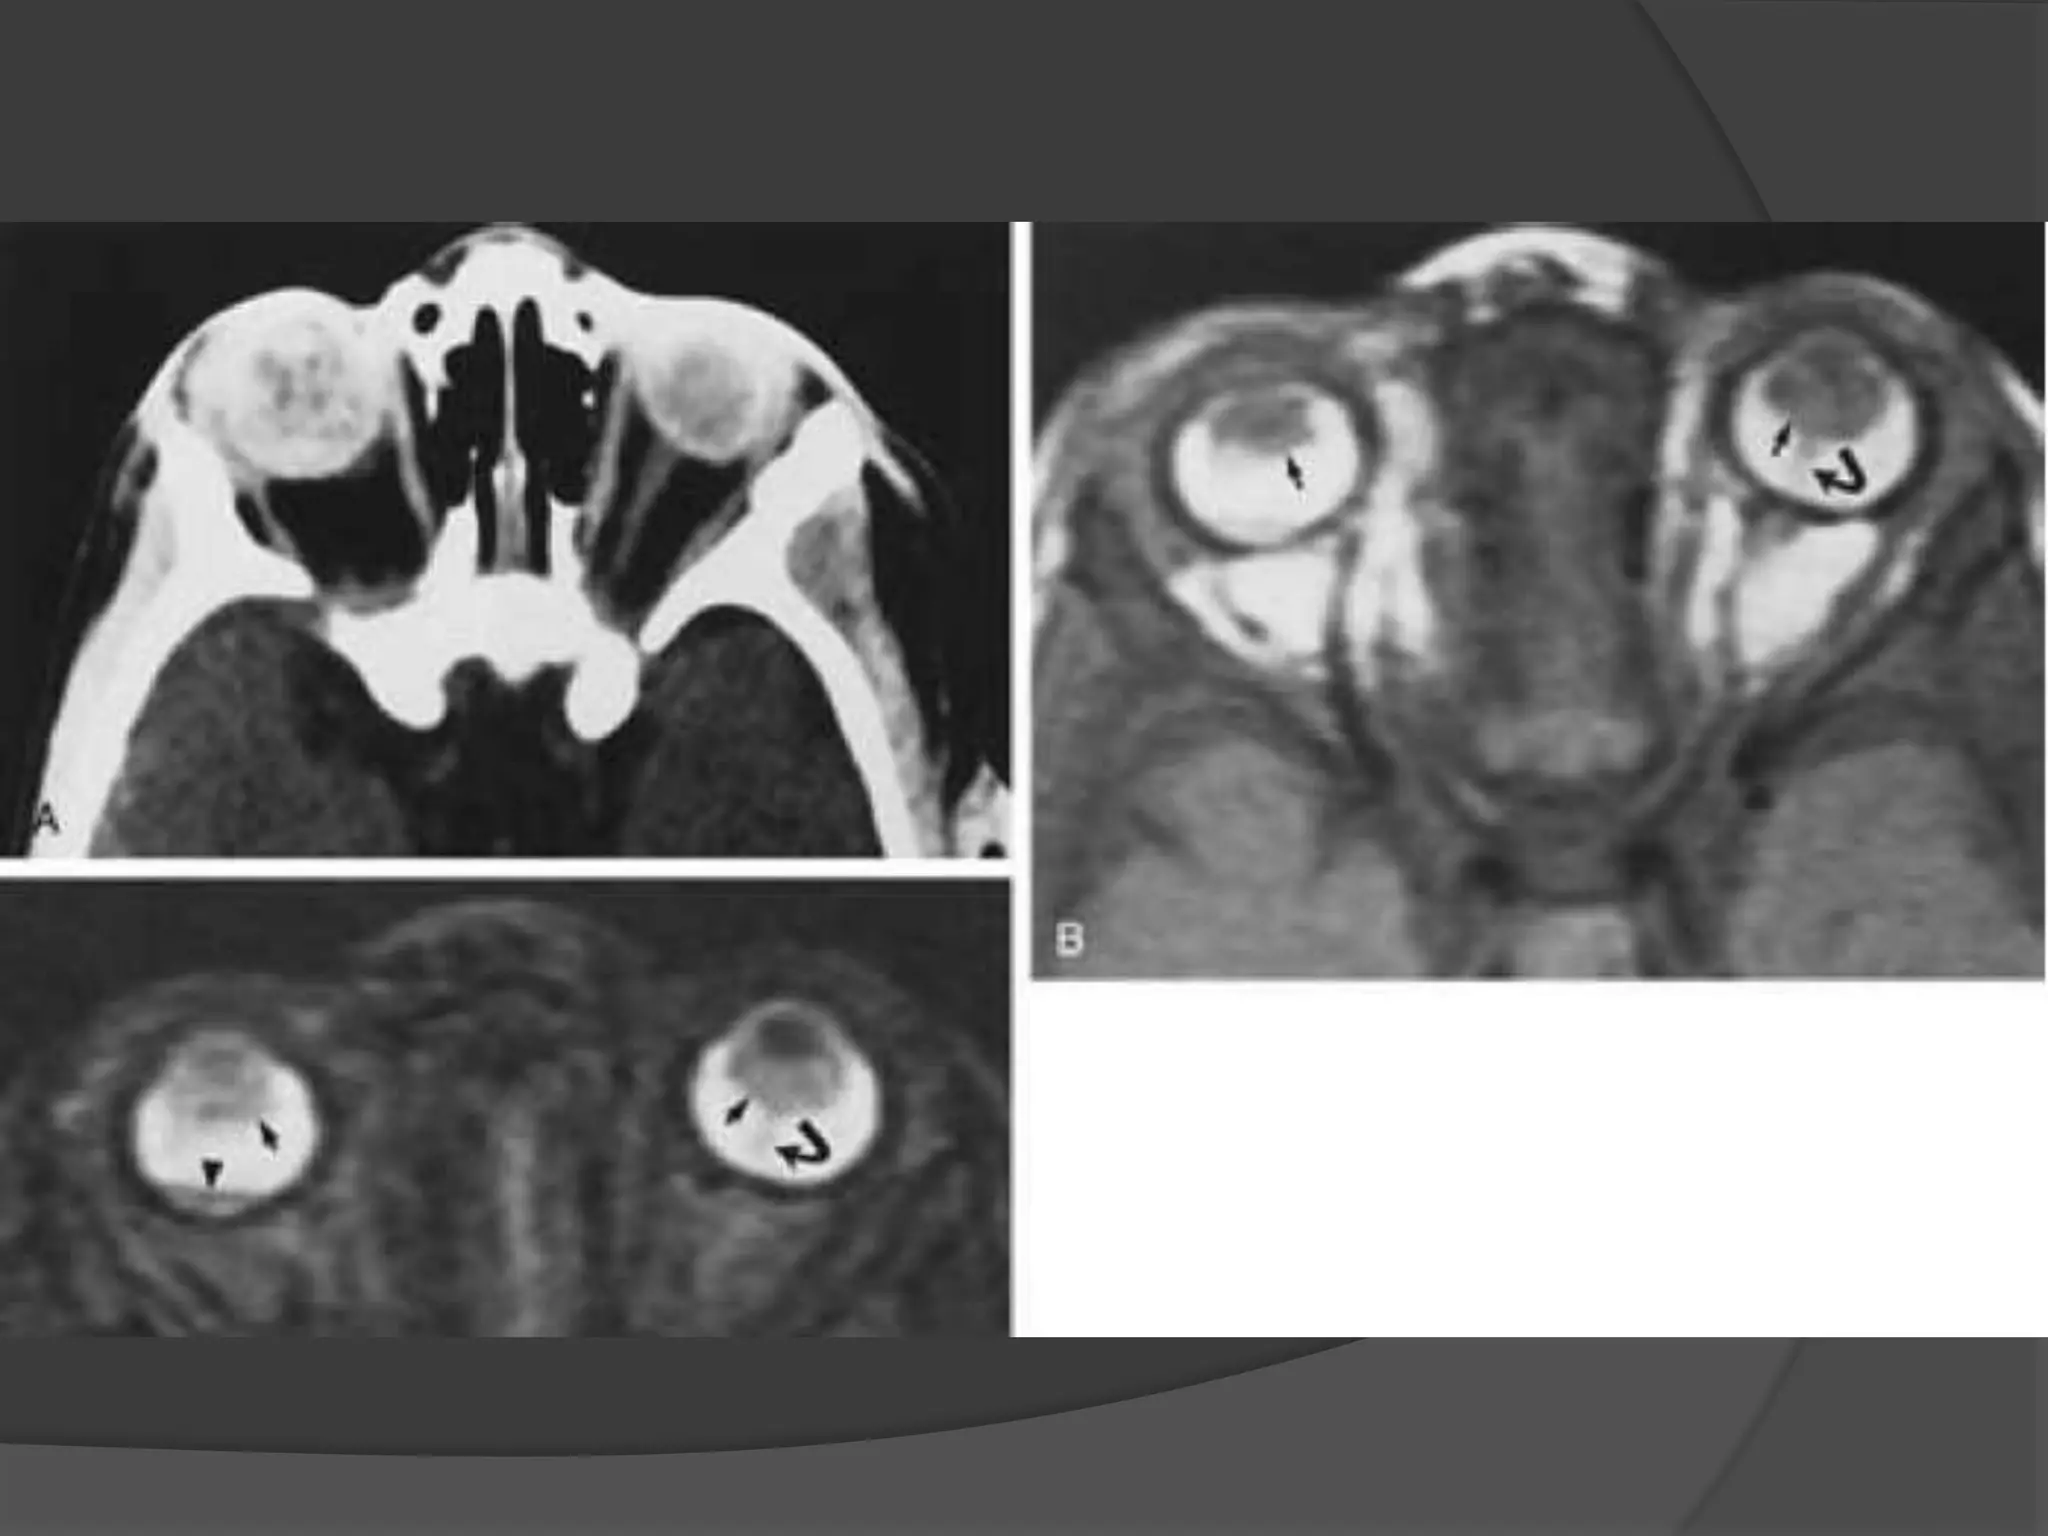

• #30 ROP. A, Axial CT scan shows increased density of the globes and left microphthalmos. B, Axial PW MR image shows hyperintensity of both globes, presumably caused by subretinal hemorrhage. Note the retrolental abnormal tissues (arrows) and detached retina (curved arrow). C, Axial T2-weighted MR image shows hyperintensity of the globes and abnormal retrolental soft tissues (arrows). Note the detached retina (curved arrow) and the layered acute hemorrhage in the right subretinal space (arrowhead ).

• #33 Coats’ disease. A, Axial CT scan shows generalized increased density of the left globe caused by bullous retinal detachment. The leaves of the detached retina are faintly seen, as shown by the arrows. B, Axial PW MR image shows hyperintensity of the left globe caused by subretinal lipoproteinaceous effusion. Note the leaves of the detached retina (arrows). C, Axial T2-weighted MR image shows the detached retina (arrows).